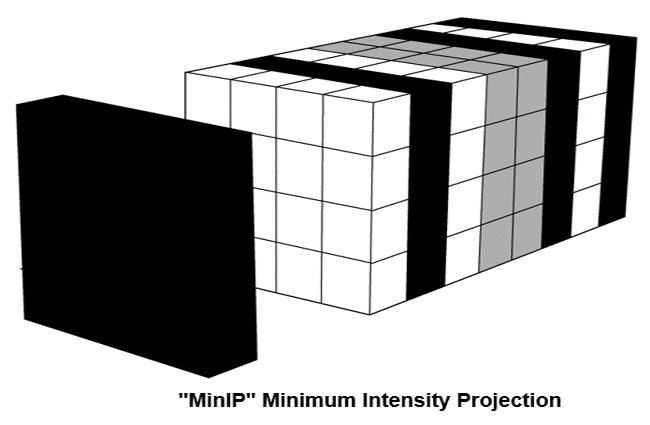

- Compare maximum intensity projection (MIP) and minimum intensity projection (MinIP)

Minimum Intensity Projection: MinIP

The Minimum Intensity projection is a data visualization method that enables the detection of low-density structures in a given volume.